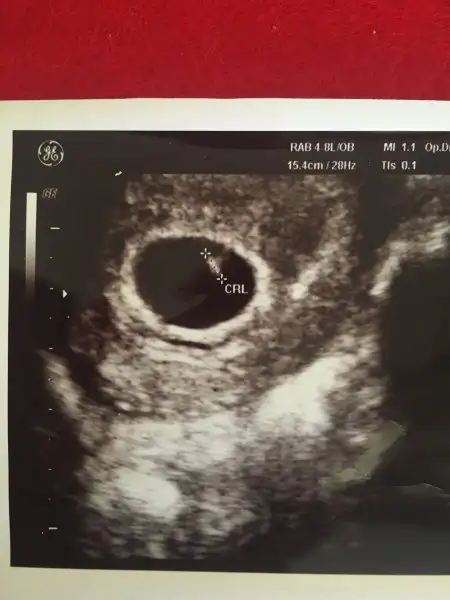

Merhaba kızlar... 6 haftalik vajinal USG Resmimi yüklüyorum bizde yorum yaparmisiniz rica etsem.